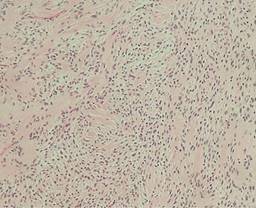

De acuerdo con la anatomía patológica, son lesiones subcutáneas, encapsuladas, caracterizadas por presentar un doble patrón histológico, las llamadas áreas de Antoni A y B.

Las áreas de Antoni A están constituidas de componente celular de la lesión, caracterizadas principalmente por presentar conglomerados densos de células de Schwann, cuyos núcleos se disponen en algunas zonas en empalizada, dando lugar a dos filas paralelas separadas por las prolongaciones de las células de Schwann, características conocidas como cuerpos de Verocay.

Las áreas de Antoni B con tendencia a presentar hipocelularidad con formación irregular predominan en un estroma mixoide laxo con vasos sanguíneos y células inflamatorias crónicas.

Posteriormente se obtiene reporte histopatológico con folio Q215-2022 que da como resultado un tumor de cuello compatible con schwannoma, con un reporte de inmunohistoquímica con resultado que describe S100 difuso (+++/+++) vimentina positivo (+++/+++) (Figuras 6 y 7).